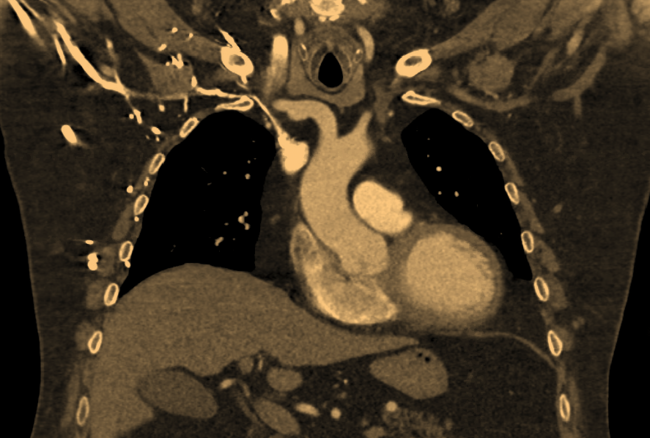

The procedure was aborted due to diminutive subclavian veins impeding access and lead placement. A chest computed tomography (CT) with contrast revealed both left and right subclavian vein narrowing, posing a barrier to conventional pacemaker implantation (Figure 1).